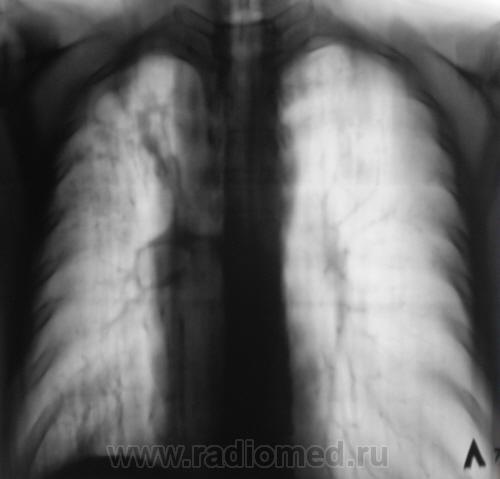

По сравнению с предыдущим исследованием зарегистрированы крупноочаговые тени средней интенсивности, хотя, по всей видимости, эти тени можно "обозвать" и мелкофокусными.

Если на фоне положительной динамики от лечения идет периодическое подсыпание... Видно,что старые очаговые изменения уплотняются, частично кальцинируются, а тут свежие, однородные... Надо искать источник.